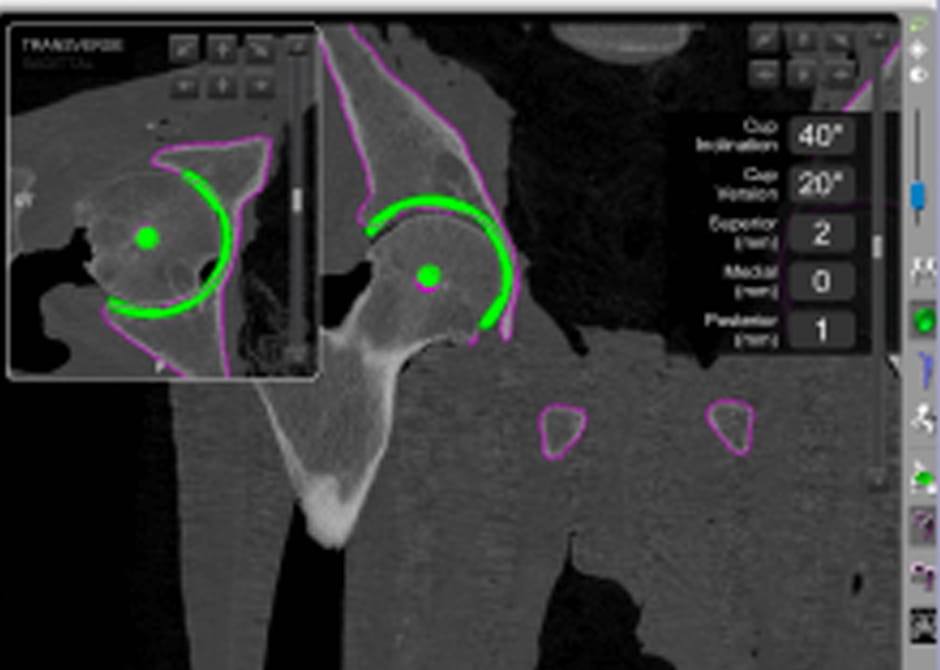

We’re constantly innovating how we treat debilitating hip pain, including using 3D models to precisely tailor each person’s surgery and performing minimally invasive procedures as well as muscle-sparing hip replacements. Our hip replacement experts will take you through each step to improving your quality of life.